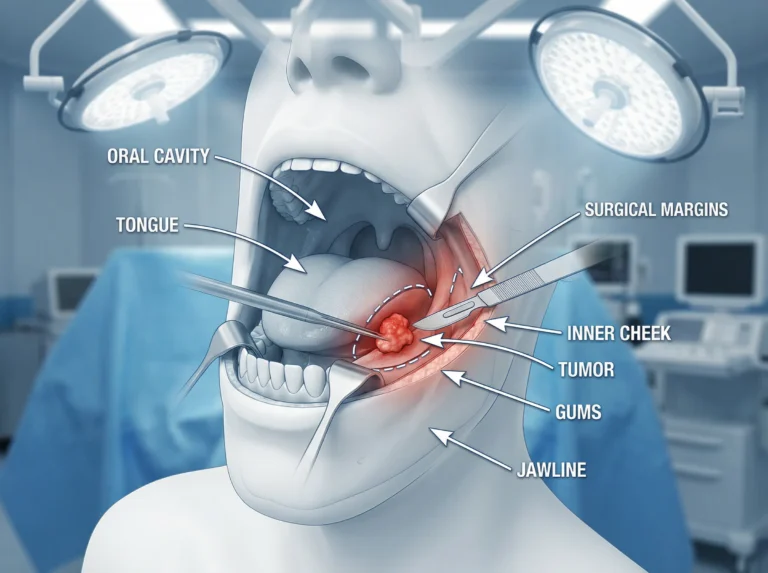

Opening the Door to Discovery Oral cancer is a life‑altering disease that affects thousands of patients every year. It begins in the…

What This Article Offers If you or your loved one has been diagnosed with oral cancer, you’re probably feeling scared, confused, or…